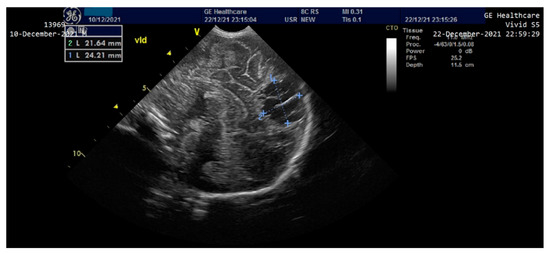

On the third day of life, the patient presented clinically and electrically generalized tonic-clonic seizures (aEEG monitoring)—requiring administration of Phenytoin (i.v) and Midazolam until the 8th day, then continued with Phenobarbital per os. A cranial ultrasound performed on the second day of life showed a round-oval hyperechoic image of 0.6/0.4 cm in the relatively superficial left frontal-parietal cerebral parenchyma which evolved to a left periventricular leukomalacia and left porencephalic cyst at one month of age (Figure 3 and Figure 4). The edema gradually reduced and the ascites disappeared; the intestinal transit became functional after 3–4 days and the enteral feeding was initiated. Parenteral nutrition was discontinued after 14 days. Neurological examination at one month of age accompanied by an EEG recording did not show any significant abnormalities. The patient was discharged after 40 days of hospitalization. At 2 months of evaluation, the patient showed an ascending weight curve and significant improvement in cytolysis and hepatic cholestasis.

Figure 4.

Cranial ultrasound at one month of age—Appearance of left periventricular leukomalacia, left porencephalic cyst.